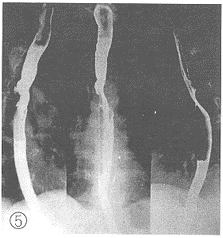

图5 食管胸上段癌,食管粘膜破坏并龛影

图6 加速放射治疗第14d,商灶管壁轮廓较前规则

2.1 X线影像比较:每例患者在术前加速放射治疗结束后第2d及第14d分别两次摄食管钡餐造影片。由放射科、放射治疗科、胸外科3名副主任医师以上的人员读片,读片前用胶布粘住每例患者的摄片的日期,再进行“多盲法”对比观察、记录。评判标准按1981年第三届全国放射学术会议(郑州)治疗组通过的食管癌放射治疗后X线诊断标准分为4级。Ⅰ级:病变完全消失,食管壁软而光滑,蠕动及扩张良好,粘膜纹理清楚可见(图1、 2);Ⅱ级:病变基本消失,食管壁规则,钡剂能顺利通过,但管壁仍僵直或狭窄,蠕动未恢复,粘膜仍增粗(图3、 4);Ⅲ级:病变明显好转,食管病灶退缩一半以上,没有明显扭曲、成角以及突出腔外的溃疡,稠的钡剂能通过(图5、 6);Ⅳ级:病变残留或恶化,病灶消退不到一半或成角,扭曲明显或有突出腔外的溃疡,钡剂通过极差(图7、 8)。118例术前加速放射治疗后不同时间的X线影像变化结果中,从Ⅲ、Ⅳ级病例上升为Ⅱ、Ⅲ级者最多,分别达 37.8%(17/45)和43.8%(7/16);但未发现越级上升和降级病例。